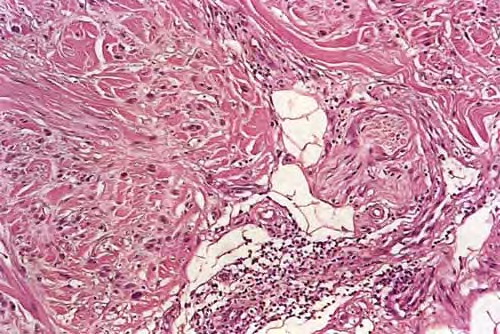

Desmoplastic melanoma = الميلانوم المكون للالتصاقات